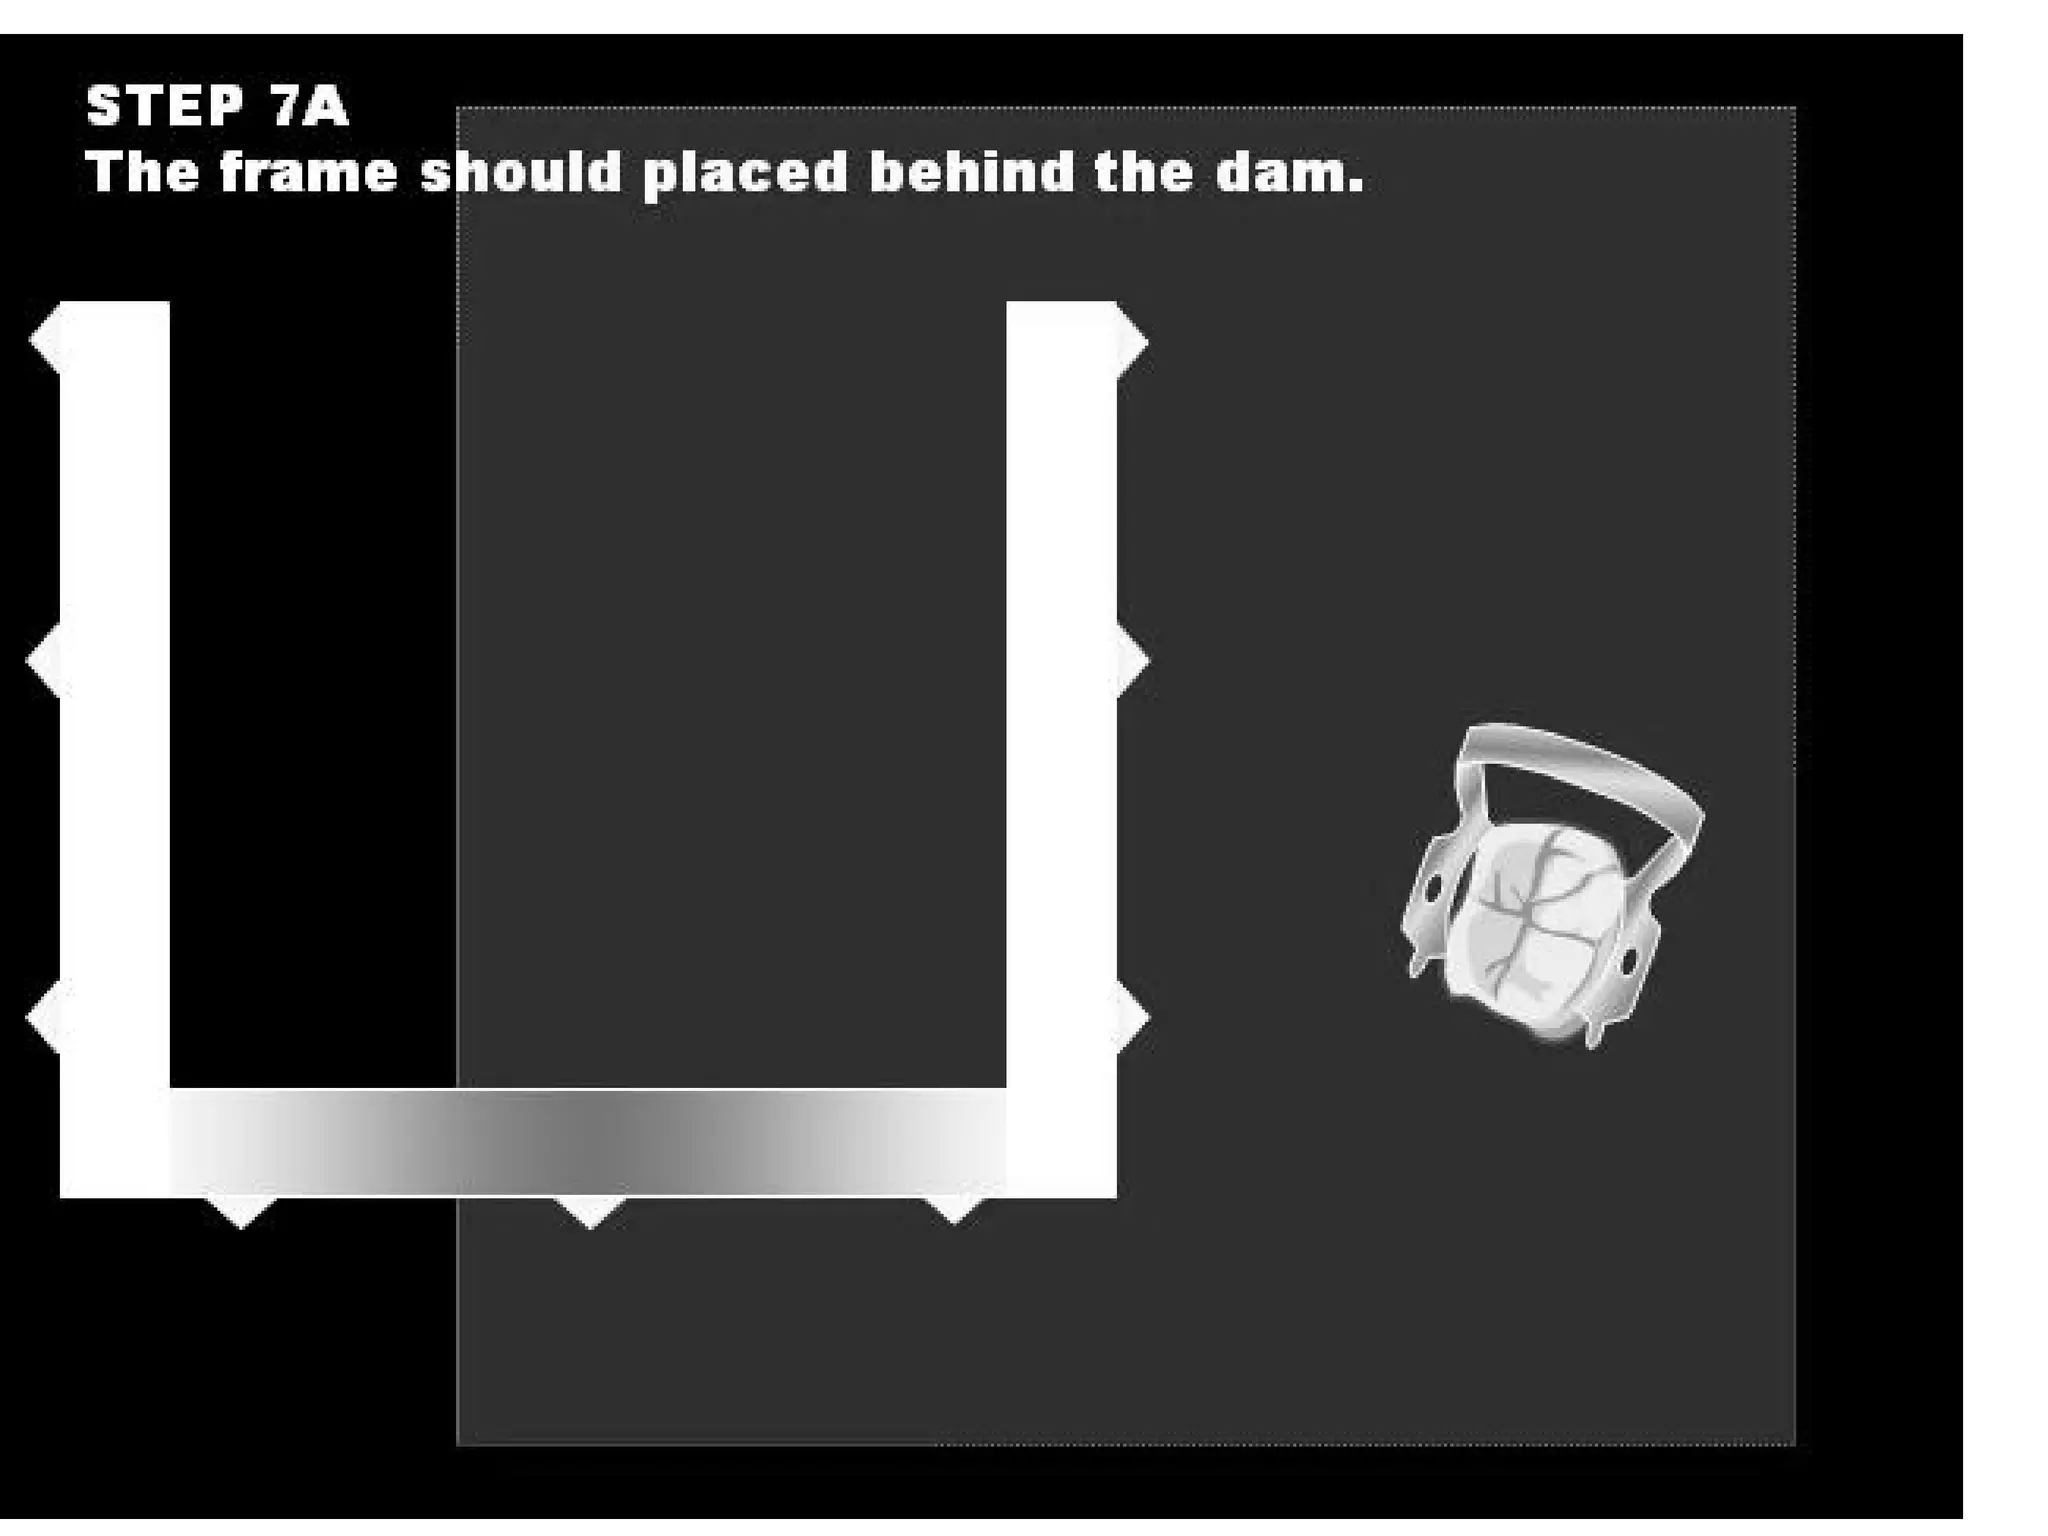

This document discusses the materials and components used for rubber dam isolation in dentistry. It describes the different types of rubber dam materials including color options and napkins to absorb moisture. It also outlines the tools needed such as punches to make holes, templates and stamps to guide hole placement, clamps to secure the dam, and other accessories like wedges and lubricant. Finally, it provides guidance on punching holes for different types of teeth and properly placing clamps in the rubber dam.